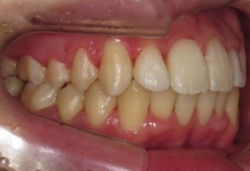

噛み合わせバランス治療(その4)

←治療前/極端なV字型.

当院での咬合治療は,状態や原因に応じて様々なシステムを組み合わせて行っています.このケースでは,前方型のスプリントにて下顎位の精査と誘導を行った後に,固定式の矯正装置(拡大装置とマルチワイヤー装置)で,対応させていただきました.

←治療前/強度な前歯の前突あり

←拡大矯正治療中.

歯列幅を,治療シュミレーションから設定した数値まで,効果的で迅速な矯正装置(緩徐拡大or急速拡大)を選択して左右的に拡大しながら,前歯の状態を整えています.

←ワイヤー矯正中

治療前と比較すると下顎は,強制的に後方に押し込まれた位置から開放されたらしく,自然に前方位を表してきました.

さらに,この下顎位にて上顎の後方歯および下顎にもワイヤー矯正を施しバランス矯正治療は終了となりました(非抜歯矯正)↓.